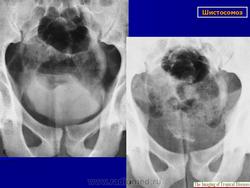

Бильгарциоз (Schistosomiasis) мочевого пузыря